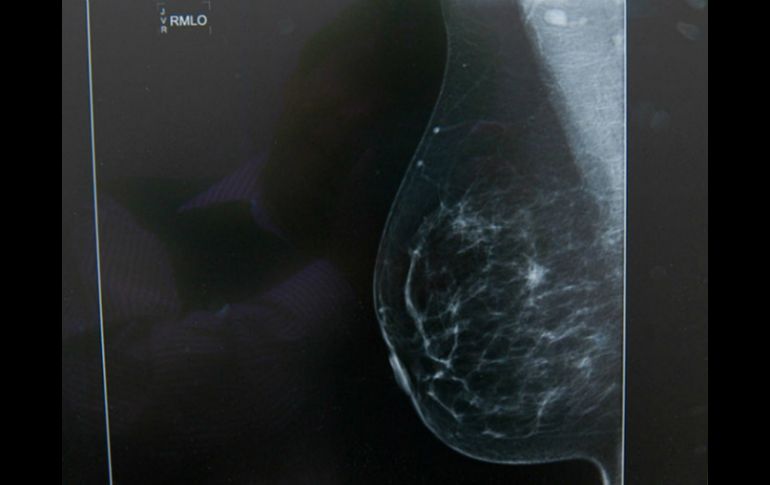

Tecnología | La técnica puede ser complementaria a los tratamientos existentes Combaten cáncer de mama con nanopartículas de plata La técnica puede ser complementaria a los tratamientos existentes de radiaciones y quimioterapias Por: NTX 26 de noviembre de 2013 - 10:06 hs Con cierta concentración de nanopartículas de plata muere 80 por ciento de las células cancerígenas. ARCHIVO / GUADALAJARA, JALISCO (26/NOV/2013).- La experta Irinea Yáñez Sánchez indicó que investigadores de tres Centros Universitarios de la Universidad de Guadalajara (UdeG) han descubierto que combatir cáncer de mama con nanopartículas de plata disminuye proliferación de células cancerígenas. La investigadora del Departamento de Ciencias Naturales del Centro Universitario de los Valles (CUValles) de la UdeG agregó que hasta el momento las pruebas han sido experimentales e in vitro (fuera del organismo vivo), por lo que no se ha practicado con animales. Añadió que gracias a la síntesis de nanoparticulas de plata en forma esférica se ha logrado tal efecto, por lo que esta técnica puede ser complementaria a los tratamientos existentes -radiaciones y quimioterapias- "para aminorar efectos adversos y tóxicos del paciente". Apuntó que "nos hace falta ver por qué disminuye la proliferación de las células cancerígenas y por qué se da la apoptosis (muerte celular), por lo que este es un proyecto de largo alcance". Señaló que los logros se deben a que con cierta concentración de nanopartículas de plata muere 80 por ciento de las células cancerígenas, "esta técnica ha sido utilizada por científicos pero en otros tamaños y con geometrías distintas; por ejemplo, para combatir el Virus de Inmunodeficiencia Humana ( VIH)". A su vez el profesor-investigador del mismo departamento, Celso Velásquez Ordoñez, expresó que la ventaja de usar plata a nivel nano es que "la actividad es muy alta y a menor costo". Explicó que al terminar las pruebas que realizan, el siguiente paso será idear un dispositivo comercial mediante el cual el organismo absorba dichos componentes, con la posibilidad de trabajar también con nanopartículas de cobre. Por su parte, el investigador del Departamento de Fisiología del Centro Universitario de Ciencias de la Salud (CUCS), Francisco Javier Gálvez Gastelum, también habló sobre el tema. Comentó que este grupo de investigación también trabaja con nanopartículas de plata (en forma de esferas y primas) para la remodelación de tejido en cicatrizaciones: hipertróficas y queloides (con bordes), y úlcera diabética. Dijo que el objetivo es saber si estas nanopartículas inhiben o estimulan el proceso de cicatrización, "pero además, para el caso de la úlcera diabética, se apuesta por un efecto bactericida, pues hay un caldo de cultivo y las bacterias colonizan esas zonas, por eso no sanan". Manifestó que las pruebas en este proyecto ya son con ratas, pero con animales sanos para ver el proceso de cicatrización. Integran también el grupo de investigación: María Luisa Ojeda Martínez, del Departamento de Ciencias Naturales del CUValles; Adalberto Zamudio Ojeda, del Departamento de Física del Centro Universitario de Ciencias Exactas e Ingenierías (CUCEI); y Trinidad García Iglesias, del Departamento de Fisiología del CUCS. Temas Investigación científica Ciencia médica Cáncer de mama Lee También Julieta Fierro será homenajeada en la FIL INAPAM: ¿Cómo solicitar un turno para consulta médica gratuita? Investigación de Rancho Izaguirre no está archivada; 12 funcionarios están involucrados Octubre Rosa: ¿Cuánto cuesta una mastografía en Jalisco según Profeco? Recibe las últimas noticias en tu e-mail Todo lo que necesitas saber para comenzar tu día Registrarse implica aceptar los Términos y Condiciones